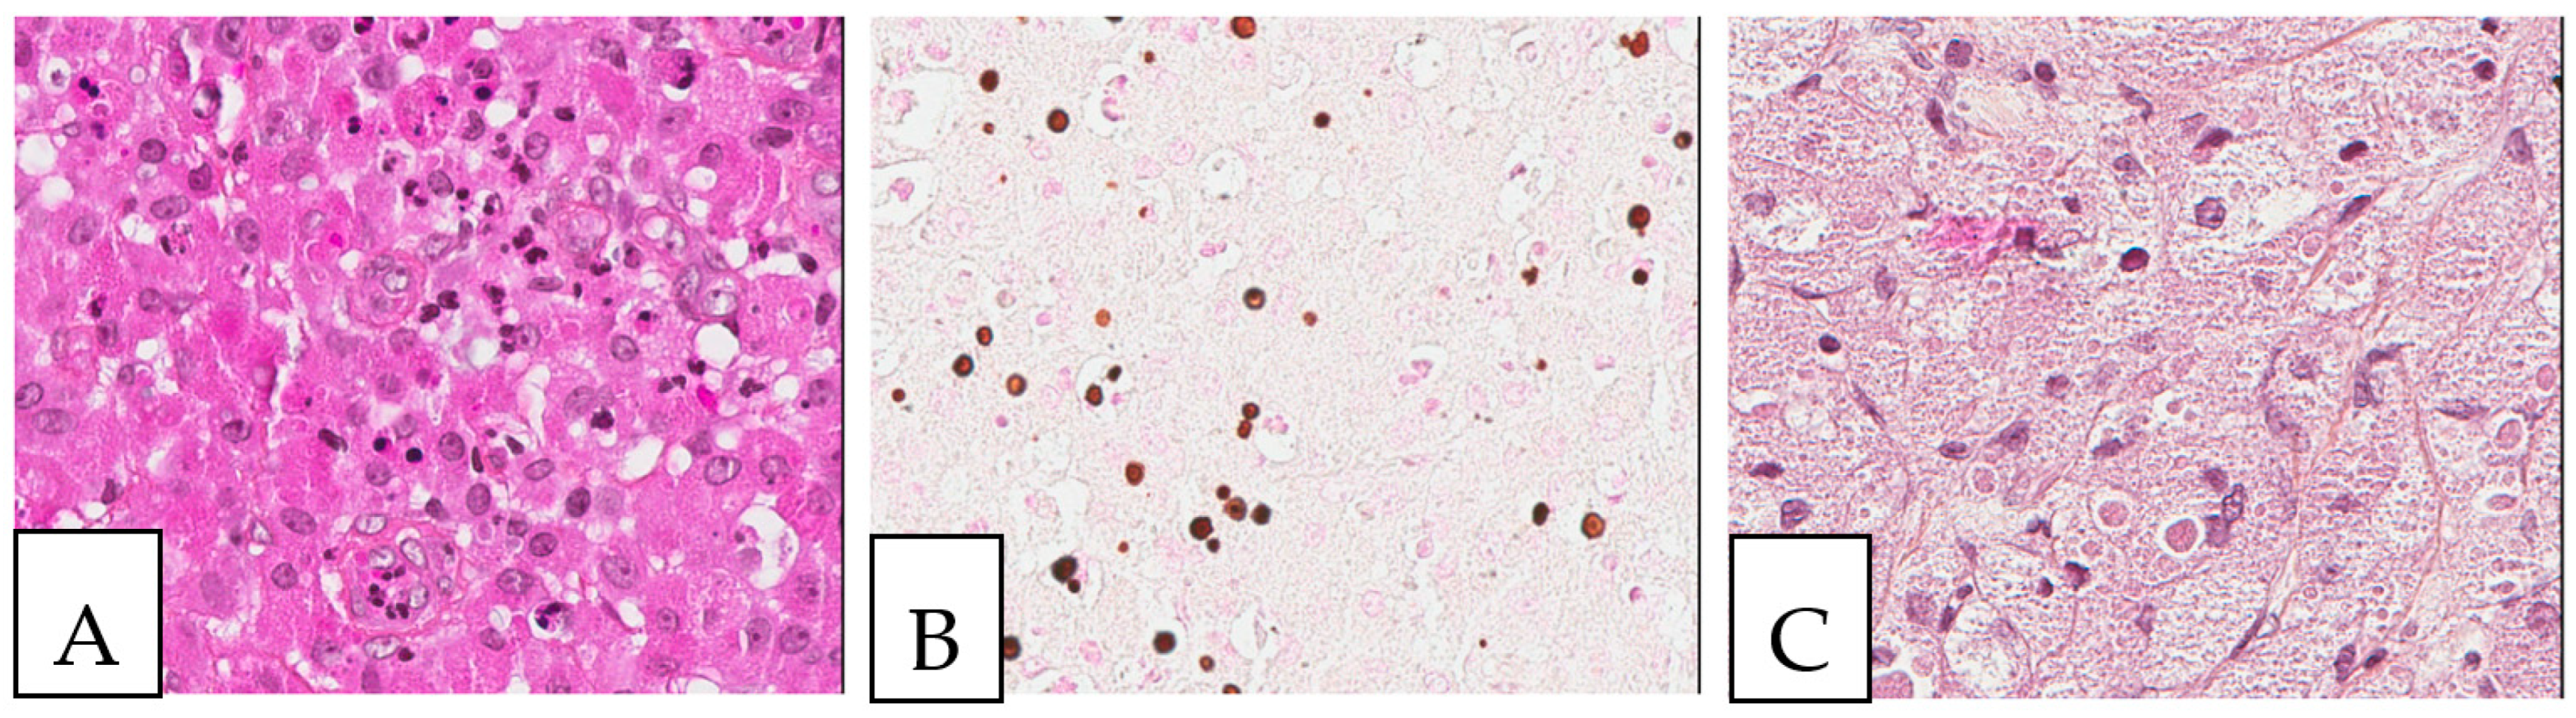

Figure 3. Malakoplakia. (A). Malakoplakia is an inflammatory process consisting of macrophages with an abundant eosinophilic cytoplasm (hematoxylin, eosin, Safran). The lesion was found in a 60-year-old male patient who underwent a colonoscopy within the context of pre-renal transplant evaluation and was found to have this lesion as a perianal polyp that was removed by polypectomy. (B). The characteristic Michaelis–Gutmann basophilic inclusions are better highlighted by the Von Kossa stain. (C). Granular cell tumor with microgranular eosinophilic cytoplasm containing the pustule-ovoid bodies of Milian (eosinophilic globules surrounded by a clear halo). This lesion presented as a reddish skin nodule in a 48-year-old-female patient.

Malakoplakia is an inflammatory condition associated with macrophages that are unable to properly digest the phagocytosed bacterial material. It typically affects the urogenital region, but many organs can be affected. Microscopically, it is characterized by a histiocytic reaction with eosinophilic cytoplasm in the inflammatory background and, sometimes, by Michaelis–Gutmann basophilic inclusions which can be demonstrated by Von Kossa stain (Figure 3). It is positive for anti-CD68 and negative for anti-S100. In contrast, granular cell tumors (Figure 3), a benign tumor type of Schwann cell origin, also with wide anatomic distribution, presents positivity for both anti-CD68 and anti-S100, with homogenous eosinophilic cytoplasm and the presence of the so-called pustule-ovoid bodies of Milian (eosinophilic globules surrounded by a clear halo). It is commonly described in the head and neck and cutaneous tissues. It is sometimes associated with pseudoepitheliomatous hyperplasia of the overlying squamous epithelium that can be mistaken for a squamous cell carcinoma.